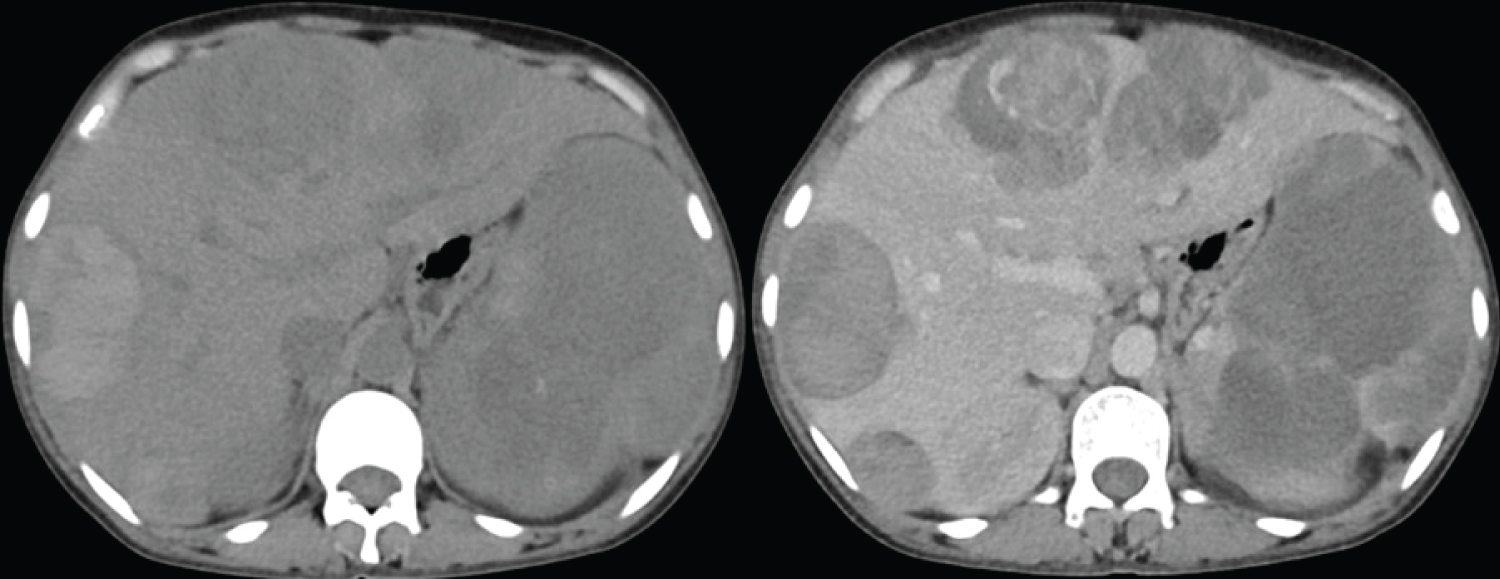

Our patient is a middle aged female who presented with vague abdominal pain and chronic diarrhoea. CECT shows two well defined lesions in segment VII/VIII and VI with intense marginal nodular enhancement in arterial phase and no washout in portal phase (Figure 2).

Figure 2: Primary NET. (a,b) Contrast enhanced CT axial sections shows a well-defined small round lesion in segment VII/VIII with intense marginal nodular enhancement in arterial phase (a) and no washout in portal phase (b) in the background of fatty liver and areas of fat sparing; (c,d) Contrast enhanced CT axial sections shows a well defined large lesion in segment VI with intense marginal nodular enhancement in arterial phase (a) and no washout in portal phase (b) in the background of fatty liver and areas of fat sparing. View Figure 2

No evidence of any focal lesion in the entire gastrointestinal tract and tracheobronchial tree.